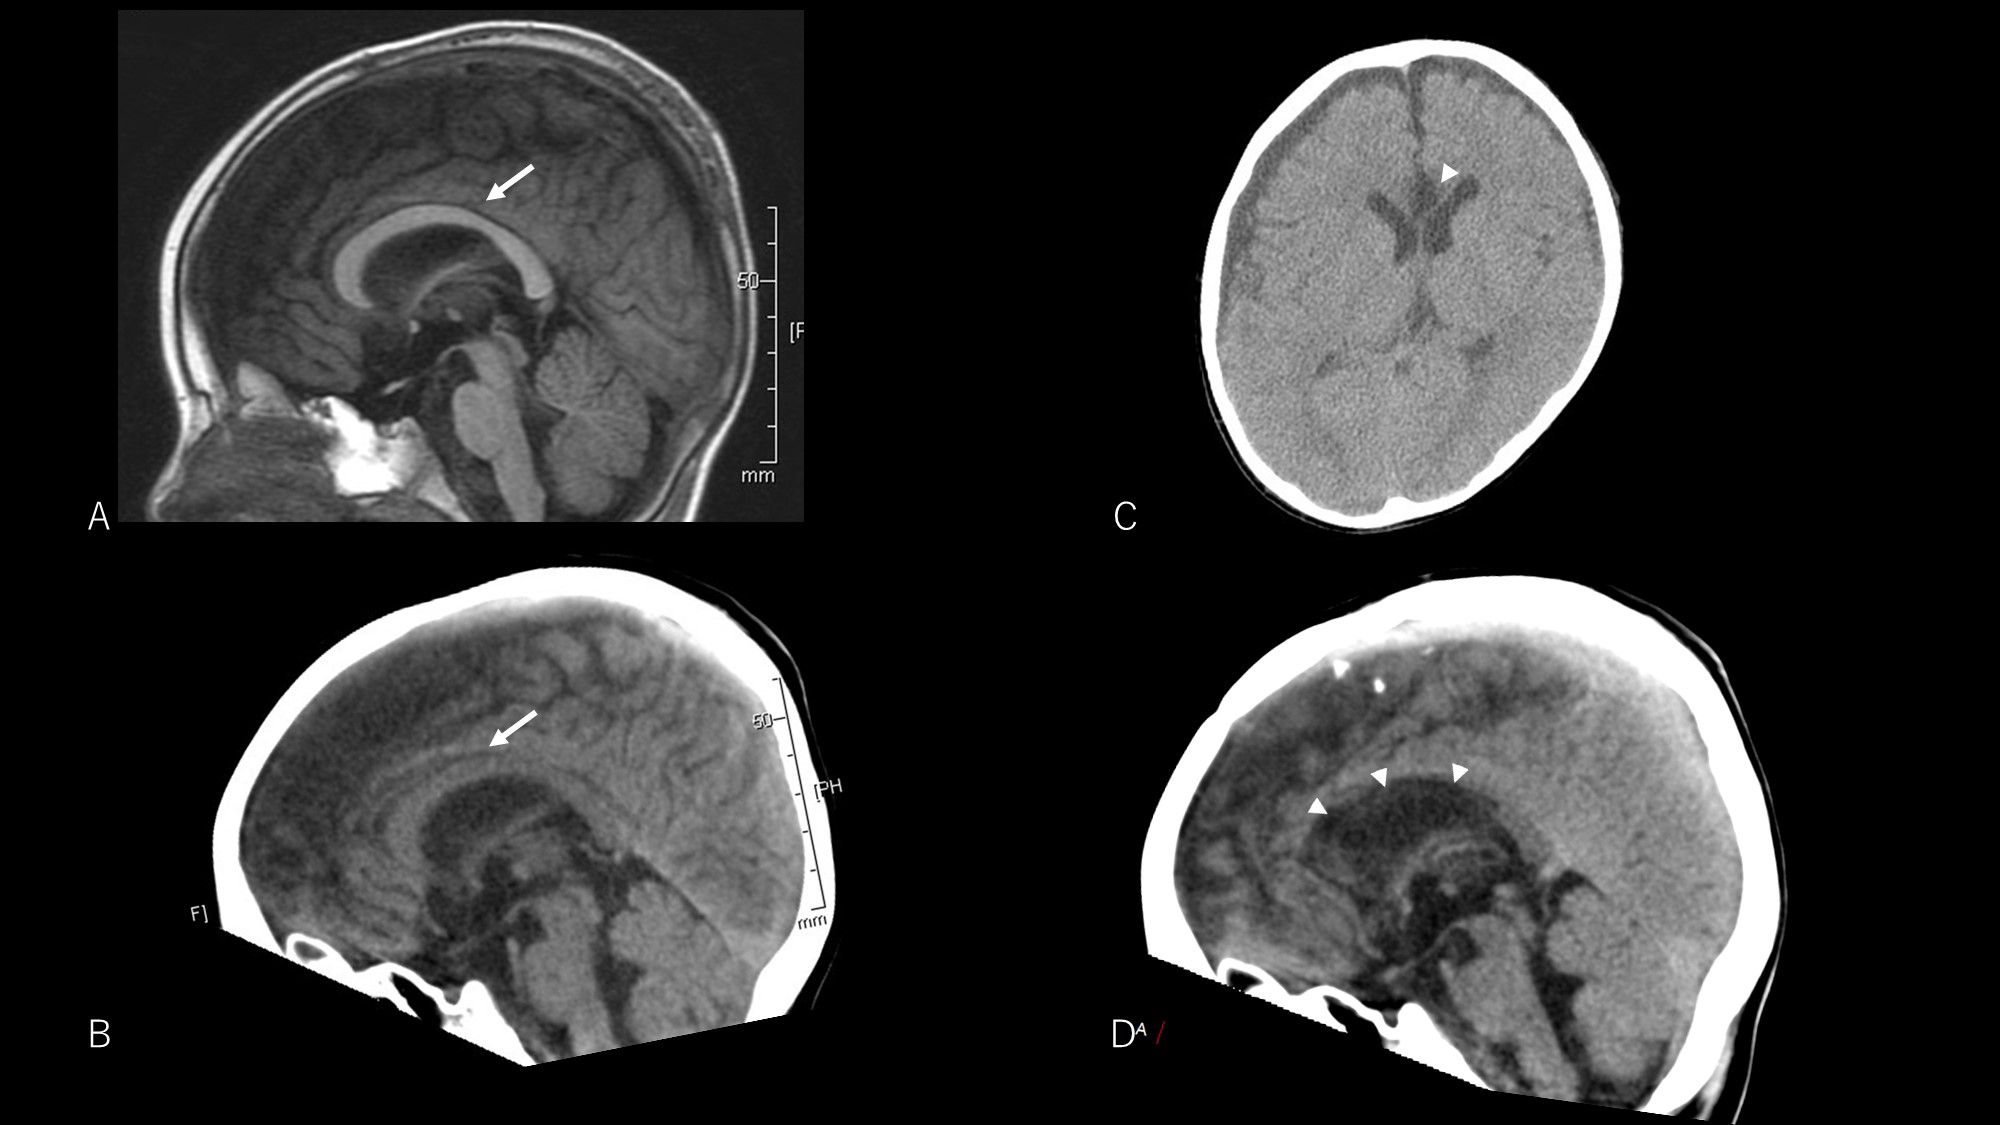

The patient experienced transient right hemispatial neglect, lasting one week. No typical disconnection syndrome was seen, including transient disturbance of consciousness. Postoperative EEG revealed a decreased frequency of bilateral synchronous discharges. The frequency of seizures was reduced to approximately 2–3 times/week. Although he still exhibited spasms, the intensity of seizures was reduced and no traumatic injury secondary to seizures was observed during the 9-month postoperative follow-up period. Postoperative computed tomography showed successful CC (Fig. 2).

Fig. 2.

Fig. 2.Pre- and postoperative neuroimaging. Preoperative T1-weighted image (A) and computed tomography (CT) image (B) both show the corpus callosum (arrow). Postoperative CT image shows a low-density area at the anterior corpus callosum (arrowheads) indicating successful corpus callosotomy (C and D).